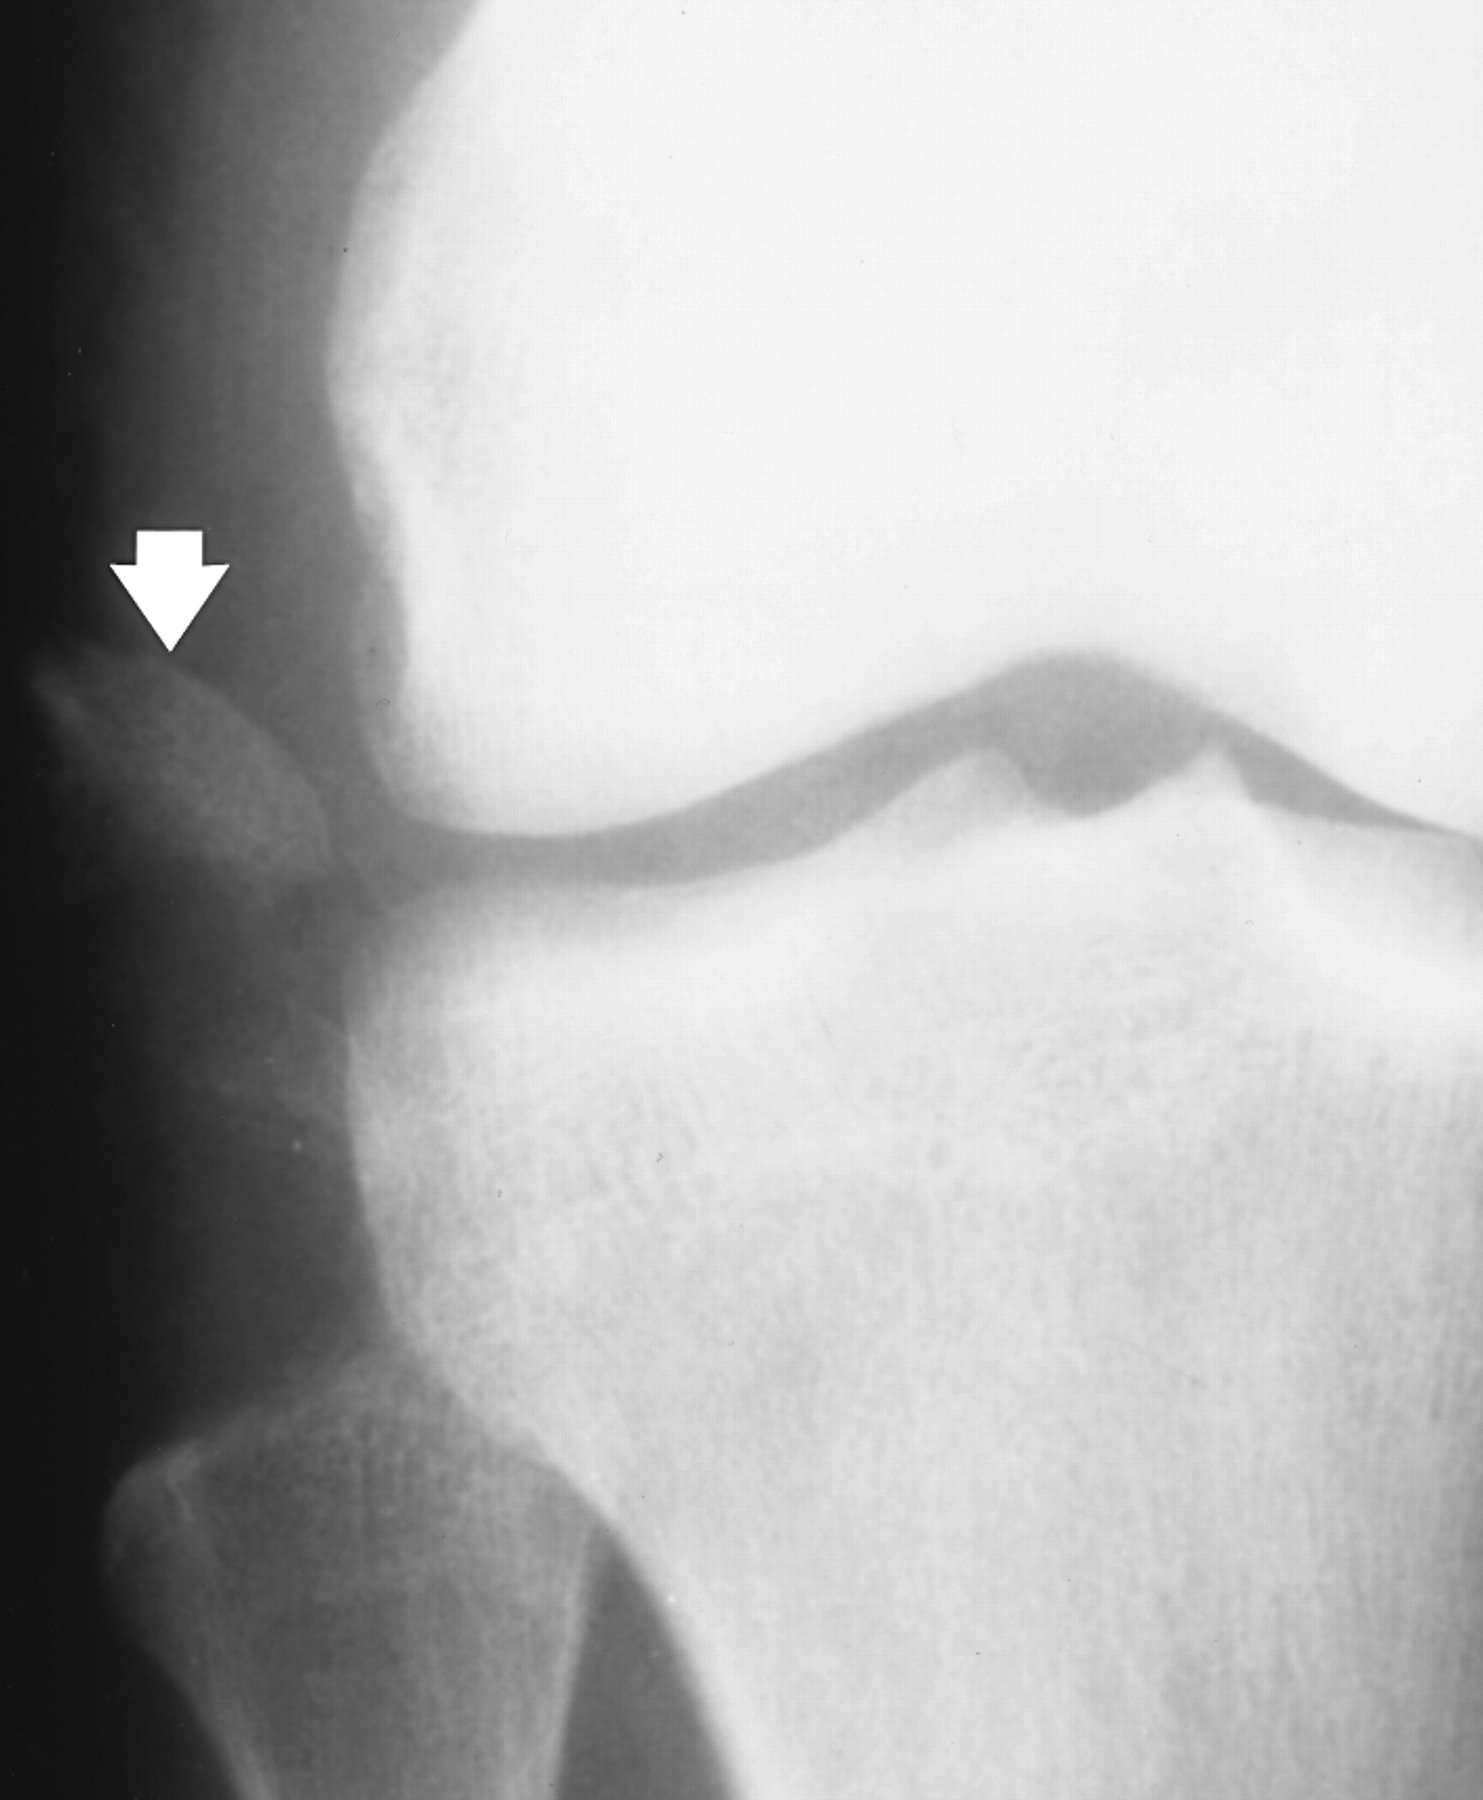

Avulsion fractures are common and easily missed. This may involve the lateral epicondyle, a Segond capsular avulsion or occasionally there is a tell tale avulsion of the tip of the fibular head indicating distraction of the lateral ligaments, this is termed the "Arcuate sign".

XRAYS

AP and Lateral views

• Many show Avulsion Fractures